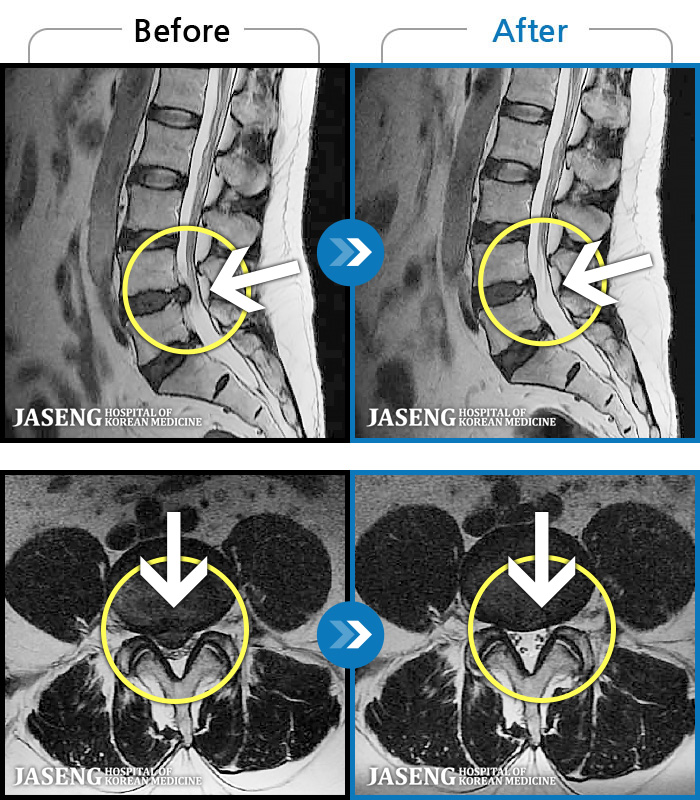

[] 03.04.01~09.11.01